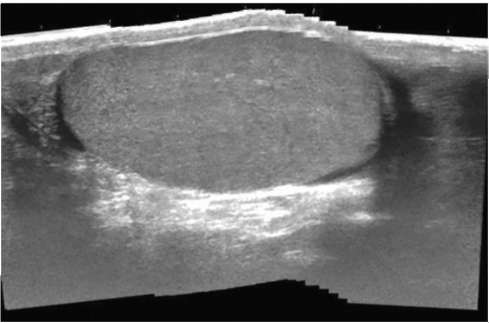

УЗИ мочевого пузыря возможно только при его адекватном наполнении мочой, когда складчатость слизистого слоя уменьшается. Визуализация мочевого пузыря возможна трансабдоминальным (рис. 4.15), трансректальным (рис. 4.16) и трансвагинальным доступом.

При УЗИ стенка мочевого пузыря имеет трехслойное строение. Средний гипоэхогенный слой представлен срединным слоем детрузора, внутренний гиперэхогенный слой является единым изображением внутреннего слоя детрузора и уротелиальной выстилки, наружный гиперэхогенный слой - изображением наружного слоя детрузора и адвентиции.

Рис. 4.15. Трансабдоминальная сонограмма мочевого пузыря в норме

Рис. 4.16. Трансректальная сонограмма мочевого пузыря в норме